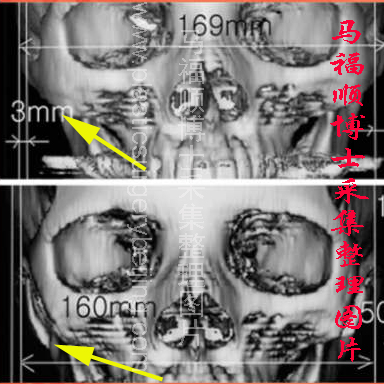

颧骨颧弓前端截骨后所致颧骨颧弓下垂,黄色箭头所指为下垂的颧骨颧弓前端已经被切开,并且向下移位,形成一个大的间隙。

颧骨颧弓骨性下垂的CT表现:三维CT图像可见颧骨颧弓的前端骨质不再连续,而是有一条明显的截骨线可见。当颧骨下垂时,截骨线后方的颧骨颧弓向内向下移位,使截骨线变宽,截骨线不再是一线形结构而是一条很宽的间隙,颧弓与下颌骨冠状突之间是的间隙变小,侧方观察颧弓与下颌骨的冠状突成像出现重叠。断层CT可见颧弓切面不连续,骨骼缺损大小可以在断层CT片上进行测量。有时可以见到骨折的两个断端显台阶状移位。